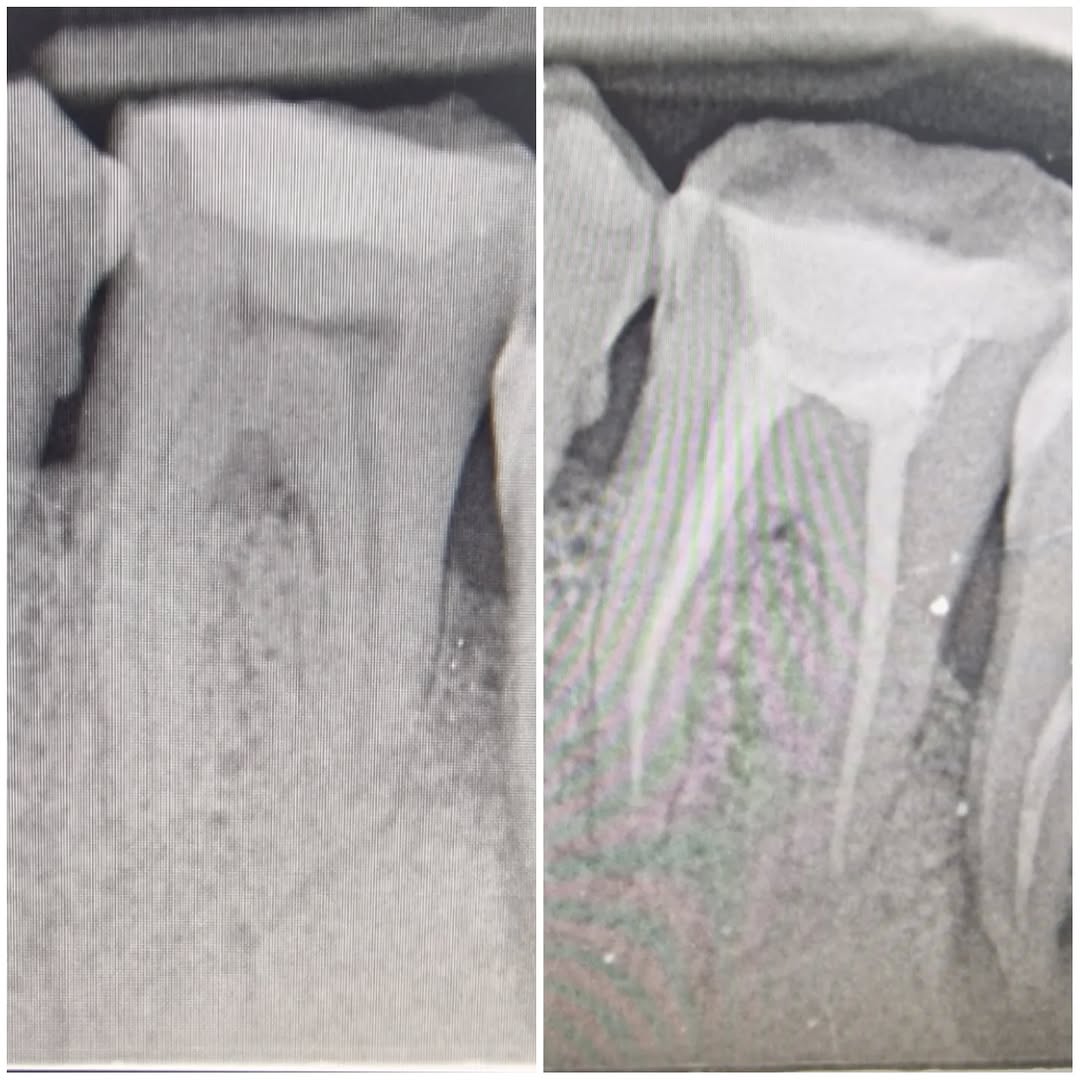

17yo patient with big decay on LR6. Second visit RCT Instrumented with ProTaper Wave One Gold. #dentist #endodontist #protaper

17